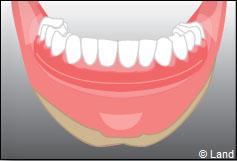

Les implants peuvent aussi servir à stabiliser un appareil amovible au maxillaire supérieur comme au maxillaire inférieur. Dans ce cas, les implants retiennent la prothèse amovible par des systèmes d’attachement.

Deux techniques sont possibles. Elles font appel à la barre de rétention ou aux boutons-pressions.